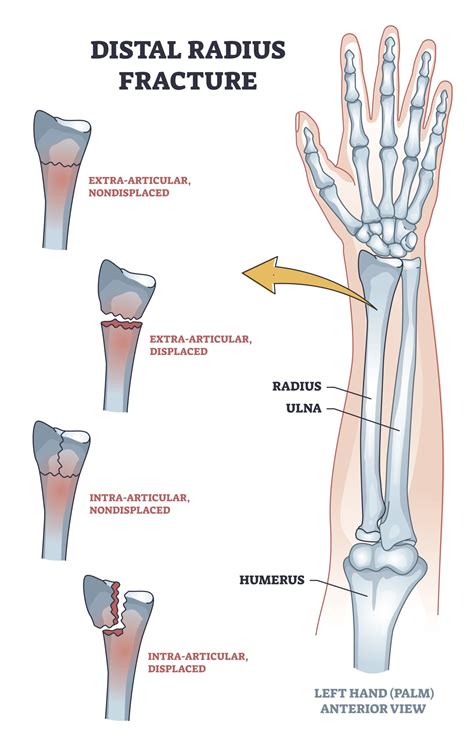

Understanding the Radius and Ulna

The radius and ulna are the two bones that make up the forearm. The radius is located on the thumb side of the forearm, while the ulna is on the little finger side. These bones work together to allow for the rotation and flexion of the forearm, enabling a wide range of movements essential for daily activities.

Diagnosing a Fractured Radius Ulna

• X-Rays: X-rays are the primary imaging tool used to confirm the presence and severity of a fracture. They provide detailed images of the bones and can show the exact location and type of fracture.